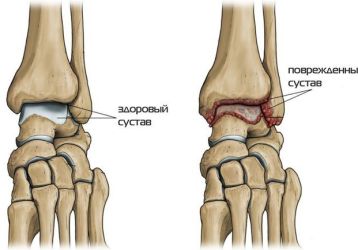

Артрит голеностопного сустава: симптомы и лечение, причины, виды, фото

Что представляет собой болезнь, артрит голеностопного сустава: симптомы и лечение, причины, диагностика. Правильное лечение артрита голеностопного сустава.